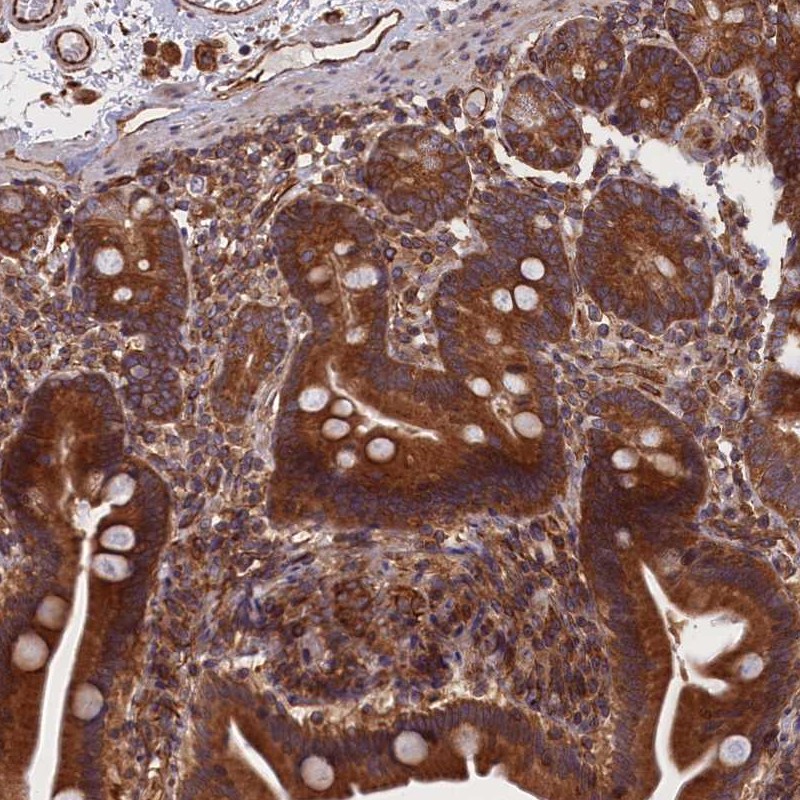

Immunohistochemical staining of human duodenum shows strong cytoplasmic positivity in glandular cells.